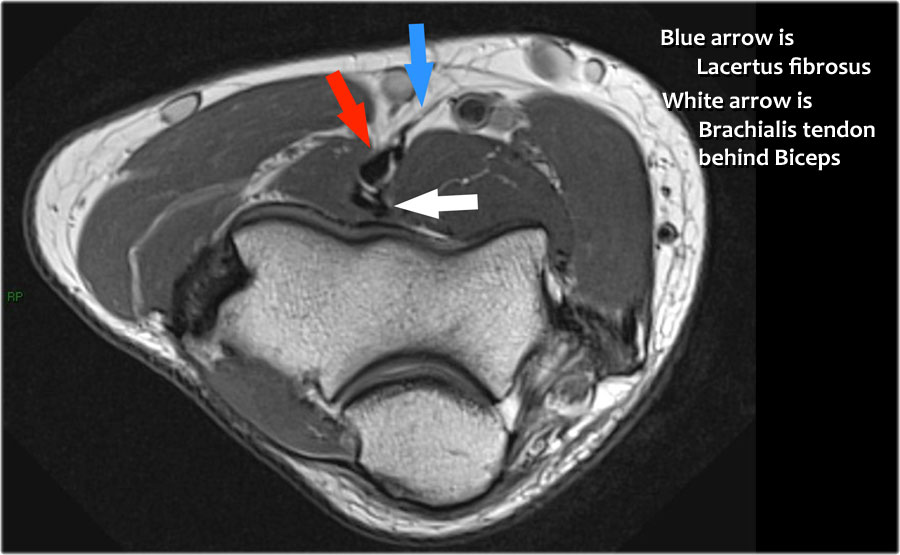

Lý do tại sao gân không bị co rút là vì cân cơ nhị đầu rộng – còn được gọi là lacertus fibrosus – vẫn còn nguyên vẹn (mũi tên đỏ).

Gân nhị đầu xa không chỉ bám vào lồi củ xương quay, mà còn thông qua lacertus fibrosus bám vào cân cơ của khối cơ gấp-sấp ở phía trong cẳng tay.

Gân xa của cơ nhị đầu được khoanh tròn ở hình ảnh phía trên bên trái.

Khi cân cơ cũng bị rách, thì gân sẽ co rút lại và bạn sẽ thấy một khối phồng rõ ràng ở cánh tay do cơ nhị đầu bị co lại.

Dây thần kinh giữa đi xuống phía sau Lacertus fibrosis, là cân cơ của cơ nhị đầu và xuyên qua cơ sấp tròn.